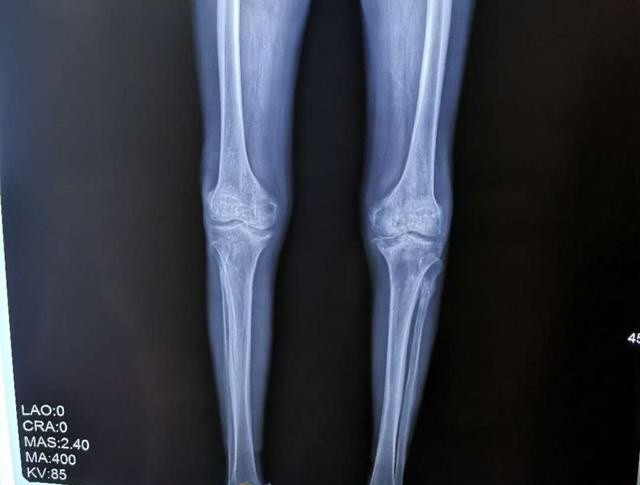

男子双膝关节严重变形罪魁祸首竟是坚持多年的习惯

图片尺寸640x485